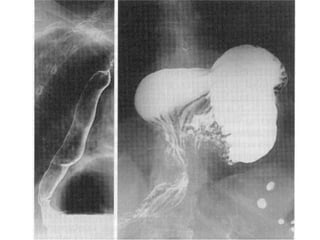

b) Espasmo esofágico difuso –

dor, disfagia e regurgitação;

associação com stress emocional;

ingestão de líquidos frios ou cólica biliar podem desencadear

espasmo;

associação com síndrome do cólon/intestino irritável.

Esófago em “quebra-nozes”, peristalse esofágica com ondas

de grande amplitude > 180 mmHg

Diagnóstico – trânsito esofágico; manometria; esofagoscopia.

Medidas sintomáticas, sedação; esofagomiotomia ?.